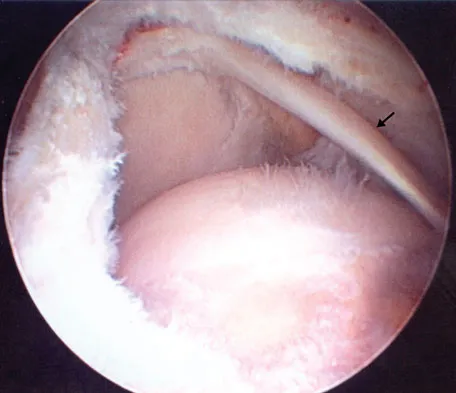

Figure 43 shows an arthroscopic view of a right shoulder through a lateral portal in the beach chair position. The arrow is pointing to what structure?

Explanation

This view from the lateral portal shows a full-thickness rotator cuff tear. The glenohumeral joint can be visualized through this tear. The glenoid, labrum, and biceps tendon attaching to the superior aspect of the glenoid are easily viewed from this portal, and the arrow is pointing to the biceps tendon. Arthroscopic rotator cuff repair can be performed while visualizing from this portal and using anterior and posterior working portals. Mazzocca AD, Noerdlinger M, Cole B, et al: Arthroscopy of the shoulder: Indications and general principles of techniques, in McGinty JB (ed): Operative Arthroscopy, ed 3. Philadelphia, PA, Lippincott Williams & Wilkins, 2003, pp 412-427.